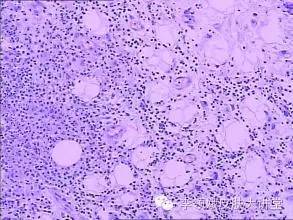

组织病理学是对皮损在微观层面的观察,是肉眼观察在更深层次的继续。诊断困难时可做特殊染色、免疫荧光及免疫组化。对某些炎性皮肤病的扁平苔藓、结核、银屑病等,不具备特征性组织病理改变,可用于协助诊断或鉴别诊断。

组织病理检查的特点 :标本的选取、取材的时机、取材的完整性、标本制作均为影响病理诊断的因素;标本制作过程工序复杂,且单次仅能提供活检部位的信息;组织病理学活检取材为创伤性检查,部分患者依从性差。

同种疾病在不同个体、病期、病变部位其组织变化可能有所差异;而类似的病理表现,也会出现在不同的疾病或者不同病期,因此,需要辨证论治。